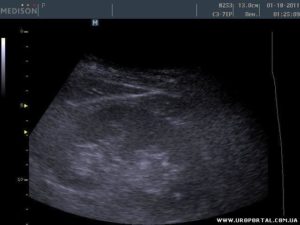

Участок с повышенной эхоплотностью визуализируется по сравнению с другими почечными тканями как более светлая зона.

Ультразвуковую волну останавливают чаще всего структуры с большой степенью плотности. Возникновение отчетливых белых пятен на снимках, сделанных во время проведения исследования, ярко свидетельствует о явном наличии в паренхиме какого-то образования.

Врач на экране монитора различает их как обширные белые участки.